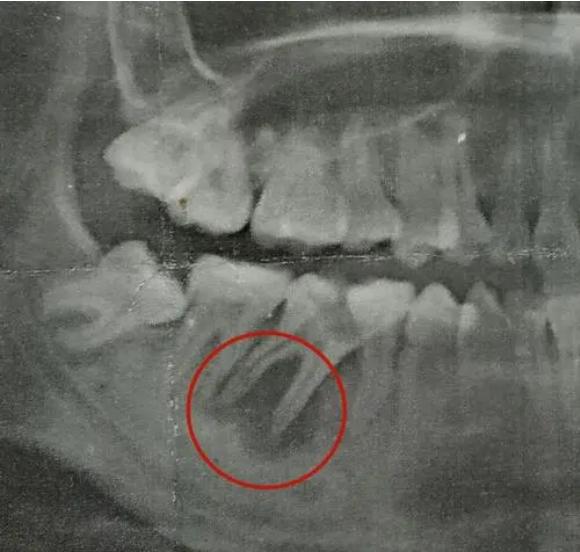

定期的口腔检查有助于提前知晓牙齿的情况,尤其是根尖炎,初期一般无法发现病症,在拍片检查的时候是能够较好地知悉口腔情况。